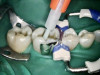

After anesthetic with 2% lidocaine with 1:100,000 epinephrine, a rubber dam was placed. The existing amalgam was removed using an inverted cone diamond bur and a small round diamond bur. The photograph showed recurrent and mesial caries. Removal of all the soft caries was performed using carbide round burs with a slow-speed handpiece. To make a clean and neat cavity preparation, all the superficial caries and stains were removed conservatively with a small round diamond bur. Then an intraoral photograph was taken to ensure that no caries was left behind (Figure 2).